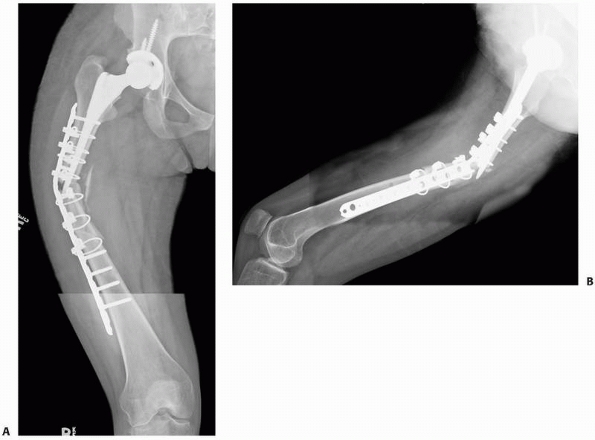

FIGURE 21-2 A,B:

High failure rates have been associated with lateral plate fixation when older direct, nonbiologically friendly reduction techniques are utilized. |

screw fixation for periprosthetic femoral shaft fractures using older

direct reduction techniques have been varied.17,28,40,47,101,103,104,152,157,164,180

Failure of traditional cable-plate constructs with cable fixation in

zone of intramedullary implant and nonlocked screws distally is likely

related, at least in part, to older direct reduction techniques and not

necessarily to the construct being inappropriate (Fig. 21-2).